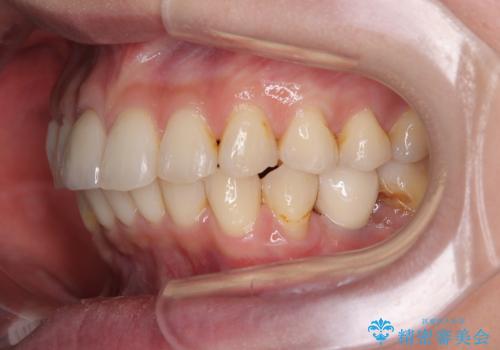

デコボコと乳歯の欠損 ワイヤー矯正とインプラント補綴治療

- 全体的なデコボコと左下乳歯部の欠損を気にして来院された患者様です。

乳歯が抜け落ちた後の後続永久歯が欠損しているため、スペースが残っておりました。

口元の突出感を気にしているのであれば欠損スペースを利用して抜歯矯正を行うことも可能ですが、横顔の印象はスッキリとしている状態であったため、矯正治療でスペースを閉じきることは不可能と判断し、インプラントによる補綴治療を行うこととしました。